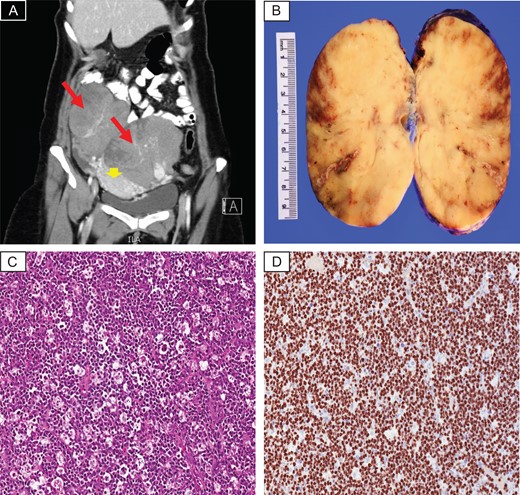

A 42-year-old lady presented to the emergency department at our hospital complaining of continuous abdominal pain and a palpable abdominal mass. No associated symptoms were identified. Physical examination demonstrated tender enlarged abdomen. Her blood work was unremarkable, except for high platelet level (480 × 109/L). Abdominal and pelvic computed tomography (CT) scan with oral and IV contrast revealed large bilateral lobulated soft tissue heterogeneous adnexal masses with some cystic components. There was an evidence of vascular enhancement within both adnexal masses. The largest mass (9.2 × 11.4 cm2). No radiological evidence of cystic rupture or hemorrhage were seen within both masses. The uterus was displaced by both adnexal masses. Both ovaries could not be visualized (Fig. 1A). Bone marrow aspirate showed mild increase in megakaryocytes with no evidence of infiltrative process. Chest x-ray and brain MRI scan were unremarkable for pathologic findings.

(A) CT scan with contrast revealed large bilateral lobulated heterogeneous adnexal masses (red arrows), displacing the uterus down (arrow head). (B) Gross photo showing homogenous white tan cut surface, focal areas of hemorrhage and necrosis are seen. (C) Histopathology examination demonstrates sheets of diffuse lymphoid infiltrate with prominent starry-sky appearance (H&E; ×20). (D) Ki67 proliferative index is almost 100% (×20).